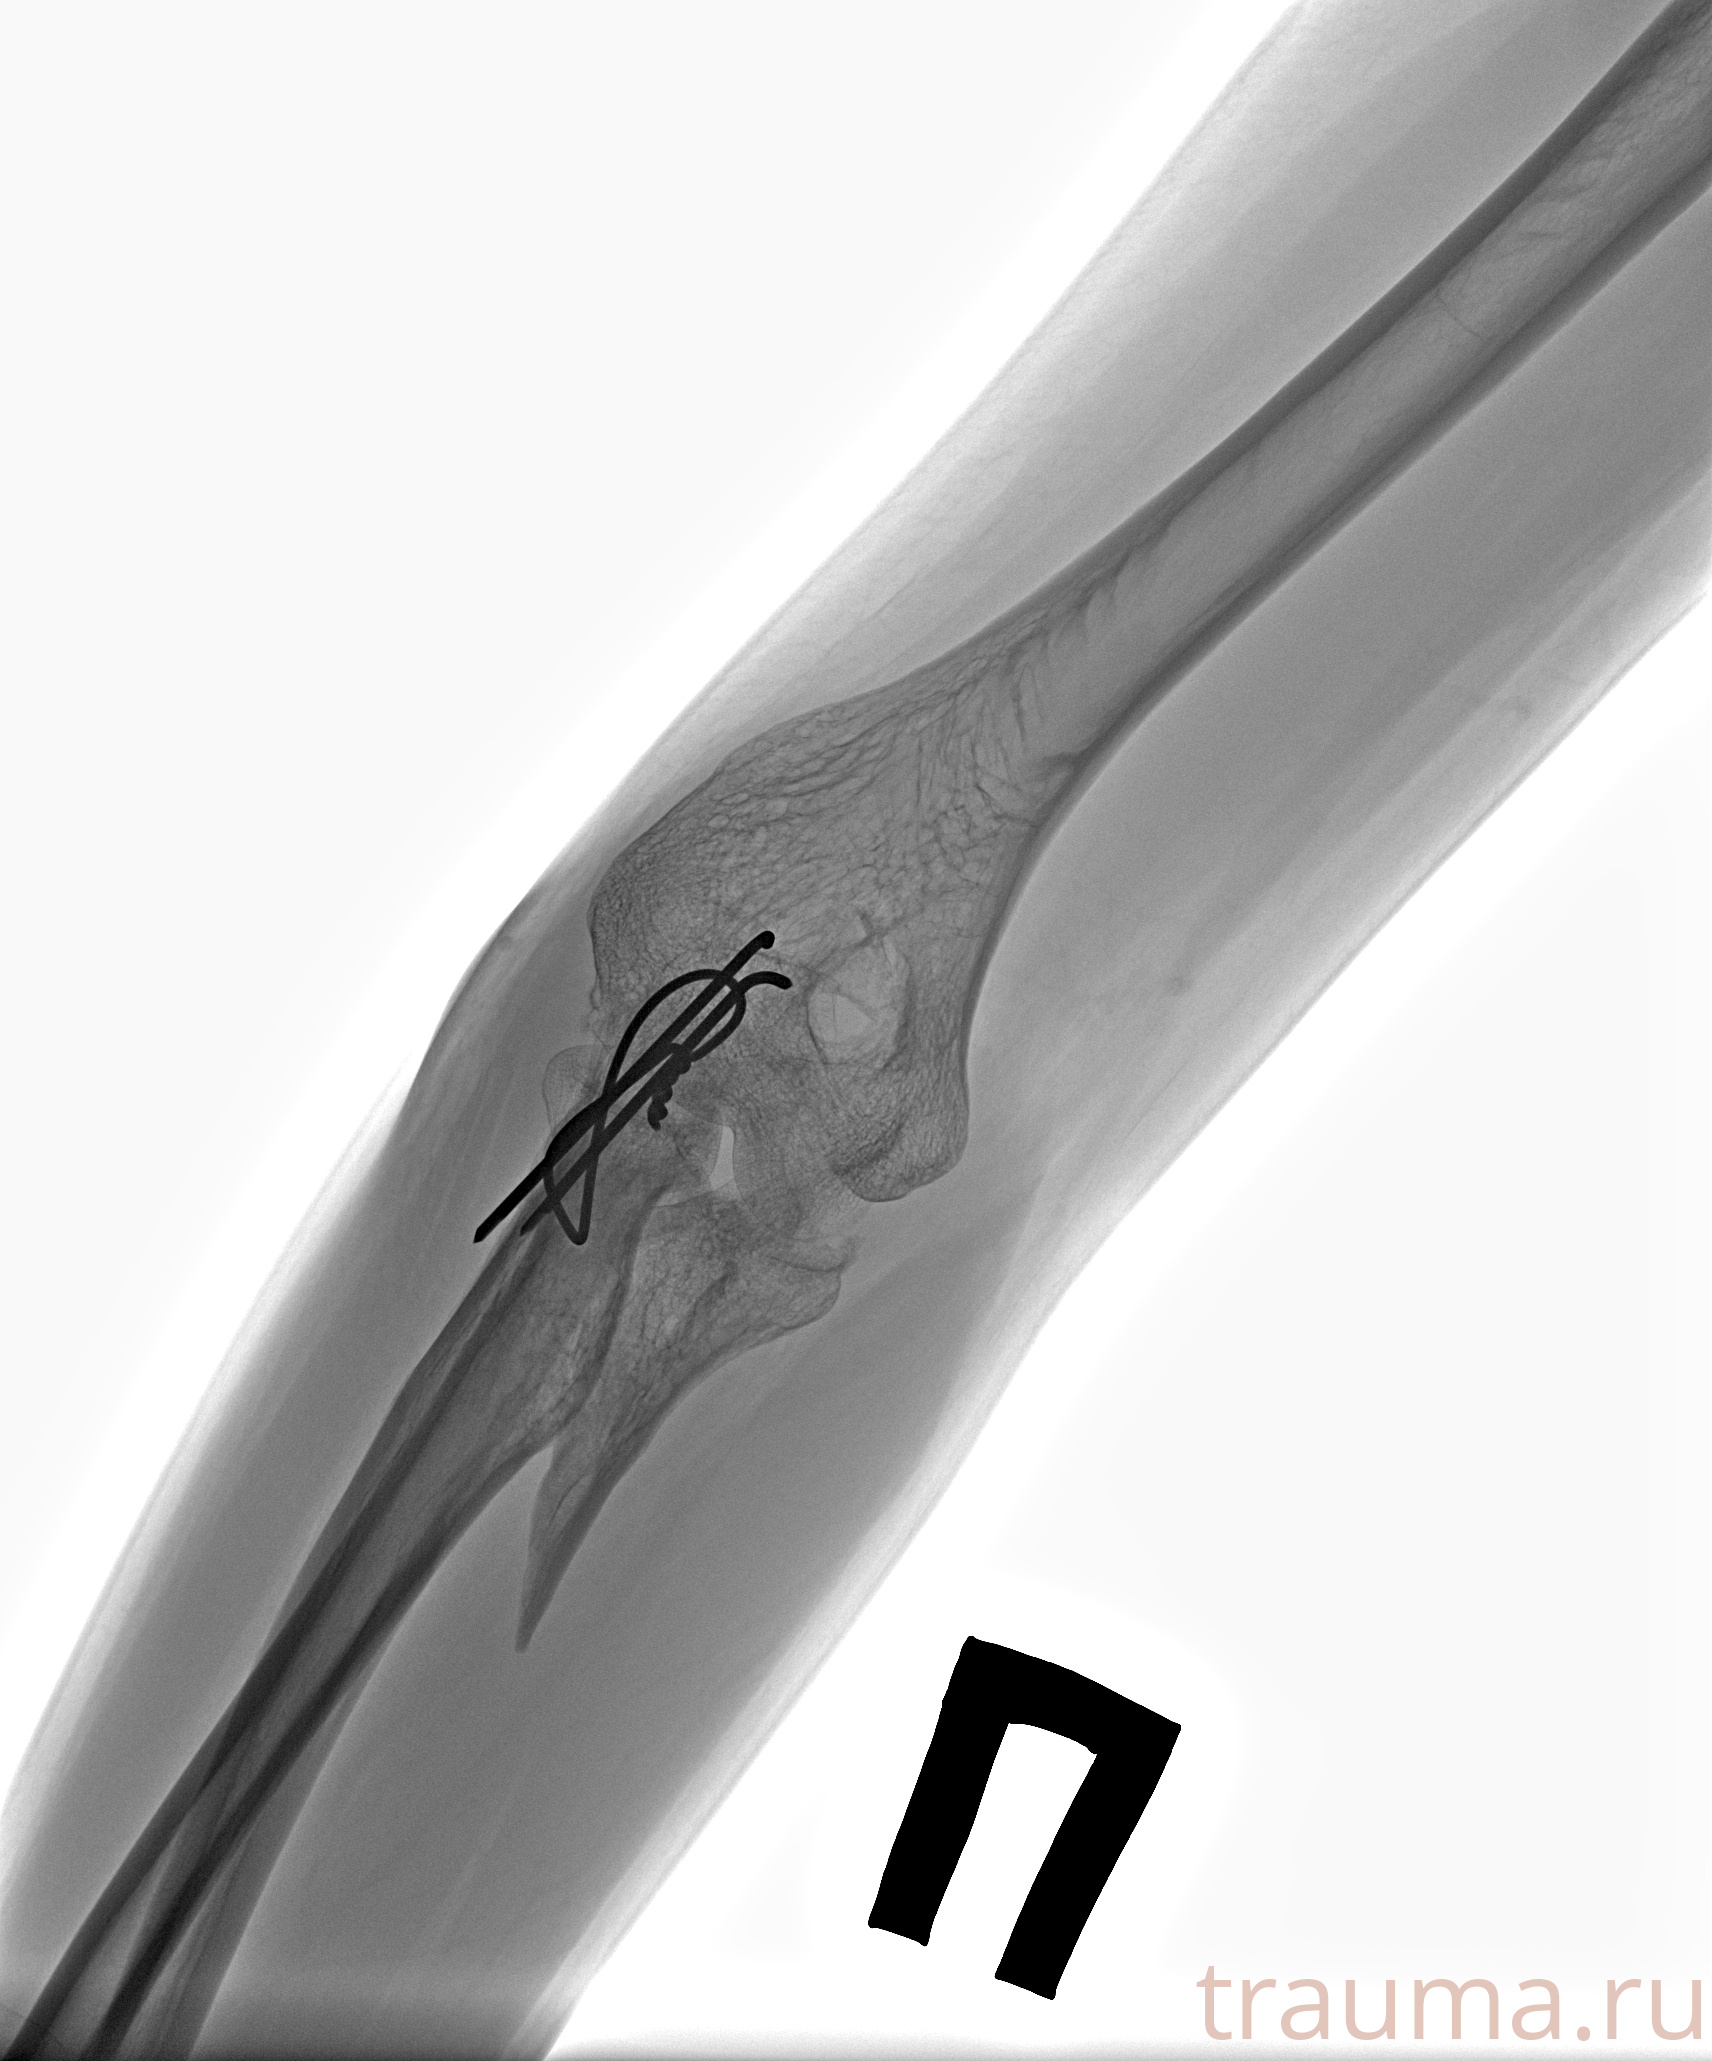

Рентген на дому: по вашему адресу приезжает врач-рентгенолог, травматолог-ортопед с мобильным рентгеновским аппаратом, проводит диагностику травмы или заболевания, делает необходимые рентгенограммы, дает рекомендации по дальнейшему лечению. Получить качественные снимки в домашних условиях возможно благодаря уникальной методике, разработанной МосРентген Центром для института  Склифосовского